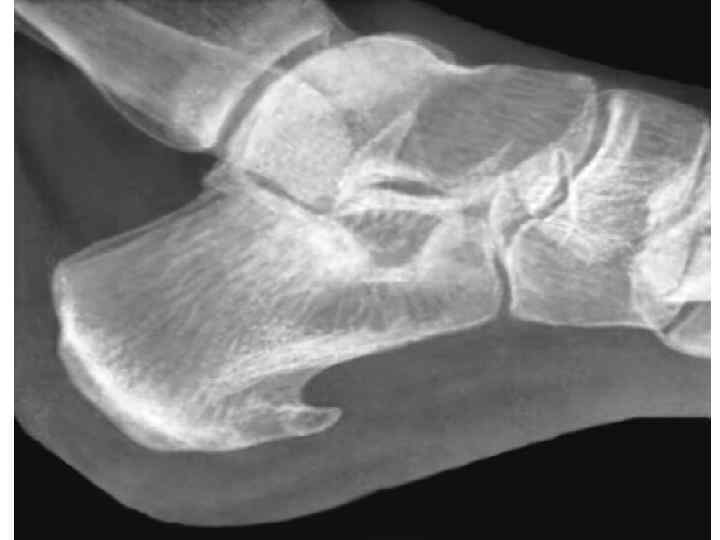

Поздние осложнения у детей • Атрофия кожи, подкожной клетчатки и мягких тканей • Запустевание лимфатических сосудов с развитием отеков • Замедление роста • Деформация костей • Укорочение облученной конечности • Асимметрия отдельных участков тела • Остеопороз • Патологические переломы • Отдаленное развитие второй злокачественной опухоли

ЛУЧЕВАЯ ТЕРАПИЯ НЕОПУХОЛЕВЫХ ЗАБОЛЕВАНИЙ ПОКАЗАНИЯ: • 1. Воспалительные заболевания кожи, ПЖК, желез хирургического профиля: фурункулы, карбункулы, абсцесс, флегмона, гидроаденит, рожа, панариций, мастит, тромбофлебит, парапроктит… • 2. П/операционные осложнения: анастомозит, фантомные боли, свищи, остеомиелит • 3. Дегенеративно-дистрофические заболевания КСА: деформирующий артроз, оссифицирующий бурсит, плече-лопаточный периартрит, пяточные шпоры и т. д. • 4. Воспалительные и гиперпластические заболевания нервной системы: сирингомиелия, неврит, радикулит, невралгия, плексит • 5. Заболевания кожи: нейродермит, зудящие дерматозы, грибковое поражение волос головы